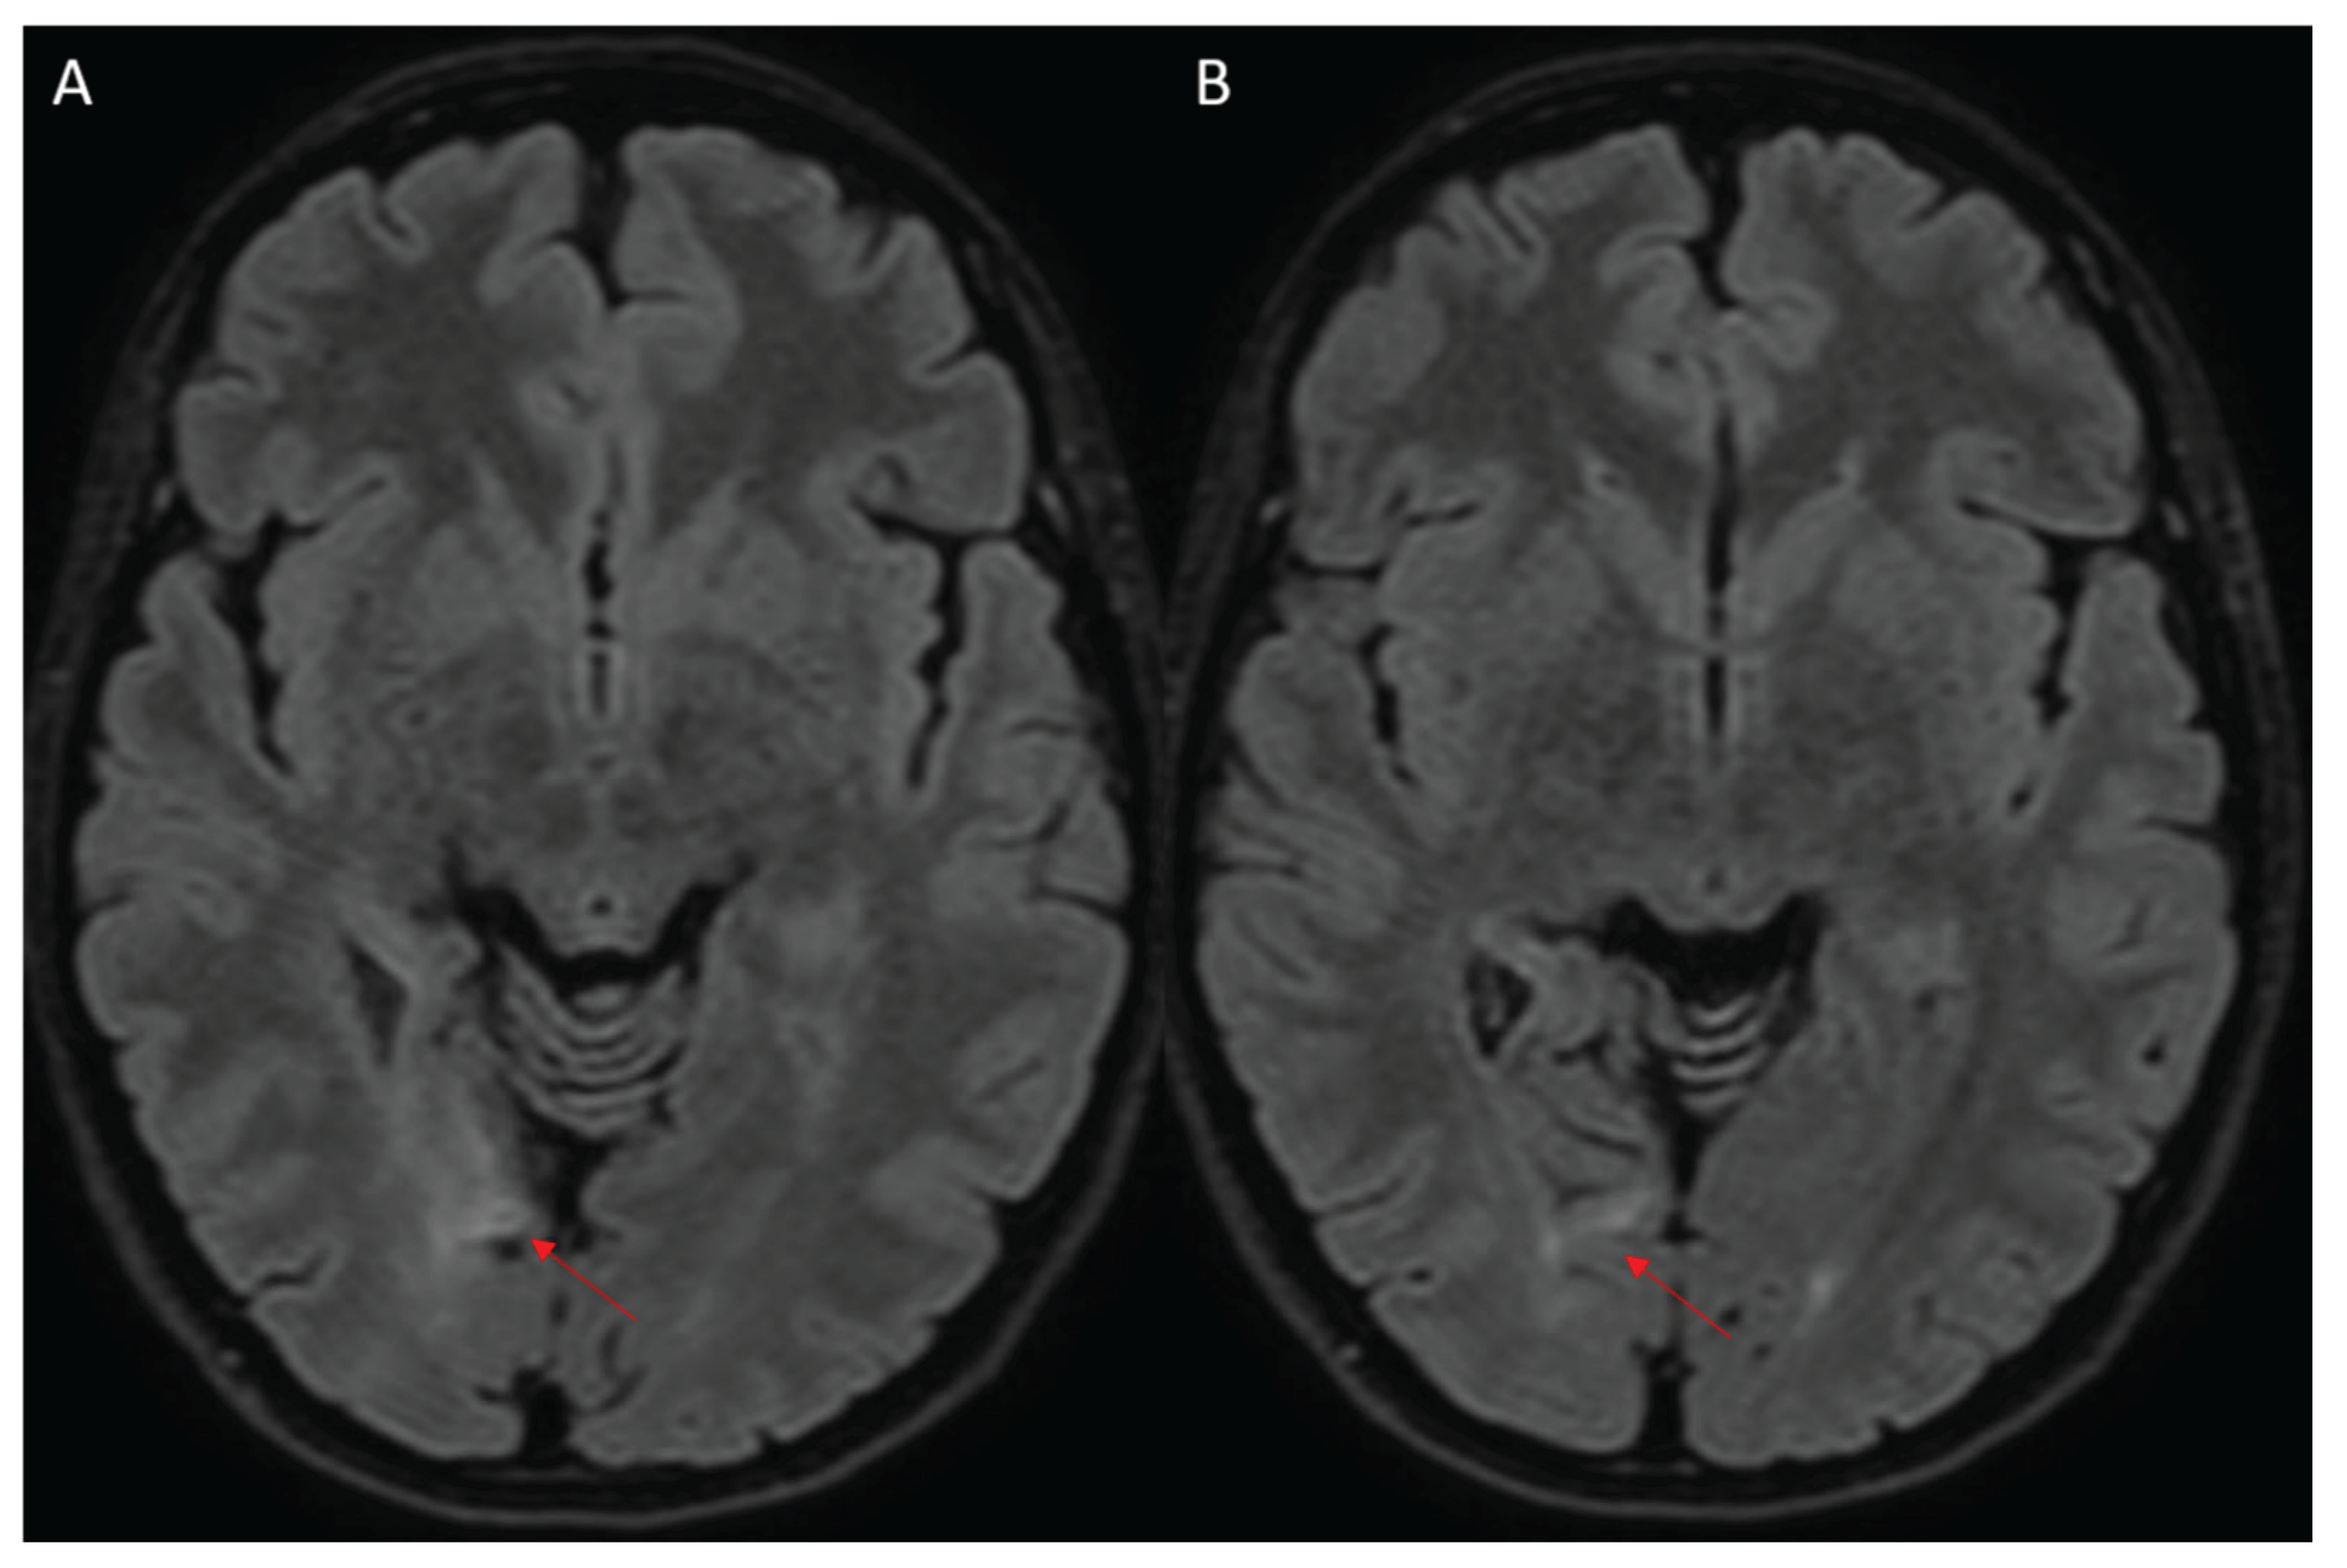

A 24-year-old woman, with a personal history of knee dislocation and mild scoliosis, suffered from a right occipital ischemic stroke (Figure 1), manifesting with sudden onset of visual disturbance and left body paresthesia. At that time, the patient started the single antiplatelet therapy (aspirin 100mg) and was discharged as minor stroke of undetermined cause [9], persisting a residual left-sided incomplete homonymous hemianopia (National Institutes of Health Stroke Scale – NIHSS: 1). After six-year follow-up with serial radiological evaluation excluding recurrences, she was finally admitted to stroke department for in-depth assessment. Herein, laboratory and instrumental tests for stroke cause identification were performed in outpatient setting: supra-aortic vessels and transcranial Doppler ultrasound, 24-hour electrocardiogram monitoring, transthoracic and transesophageal echocardiography, brain computed tomography (CT) and magnetic resonance angiography (MRA) (Figure 2), and autoantibody panel for autoimmune disease. In addition, a thorough genetic screening included hereditary thrombophilia testing performed by dot blot technique, lysosomal storage and mitochondrial diseases, and a molecular analysis of a panel of genes associated to juvenile stroke assessed with next-generation sequencing (NGS).

Figure 1. Initial Magnetic resonance imaging (MRI) showing right occipital cortical-subcortical ischemic stroke (red arrows, A-B), in fluid attenuated inversion recovery (FLAIR) sequences.